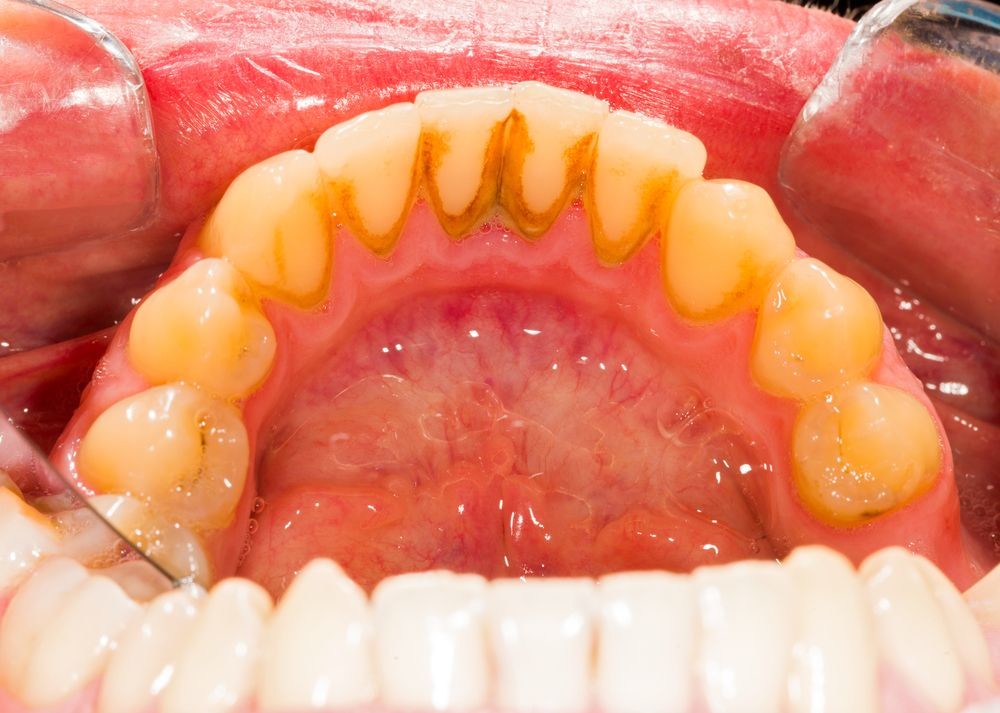

Control of oral biofilm:

Owing to the vast implications of oral biofilm for dental and general health, its effective control represents a major challenge. There is no question that the formation and maturation of oral biofilm need to be tackled by dental professionals across all specialties in all countries worldwide.

“The backbone of any therapeutic and preventive approach is the disruption of the intra-oral biofilm. An example of technologies that have been successfully demonstrated to aid supra- and subgingival instrumentation are air polishing devices with low-abrasive powders that can disrupt the biofilm on all intra-oral surfaces, including mucous membranes and difficult-to-reach subgingival areas, without harming the hard tissue and the even more vulnerable soft tissue,” Beikler explained. “Their effects can be augmented by antimicrobial and immune- and microbiome-modulating strategies. Regarding the latter, probiotics offer an interesting and promising alternative to the use of unspecific antimicrobial agents like chlorhexidine or phenolic compounds. However, additional research, that is, appropriately designed and well-structured multicentre clinical trials, is critically needed to fully appraise their therapeutic effects,” he continued.

Education on oral biofilm:

Until the early 1990s, dentists confined their treatment for combating oral plaque to removing calculus twice a year because there was only limited understanding of biofilm. Over the past decades, research on and improved knowledge about the parameters that determine the development of oral disease have spurred the development of new preventive strategies. For instance, piezoceramic instruments and low-abrasion powders have made professional biofilm management safer, minimally invasive and more comfortable for both the patient and the dental practitioner. Moreover, the launch and further development of AIRFLOW devices by EMS fundamentally changed biofilm management and eventually resulted in the development of Guided Biofilm Therapy, an innovative concept for contemporary prophylaxis.